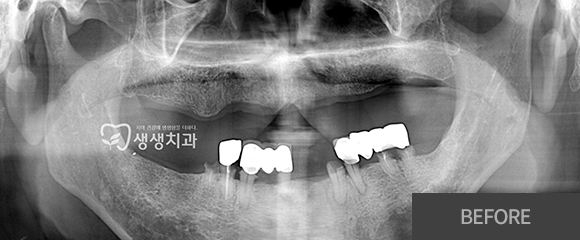

전악(전체) 임플란트

CASE 1